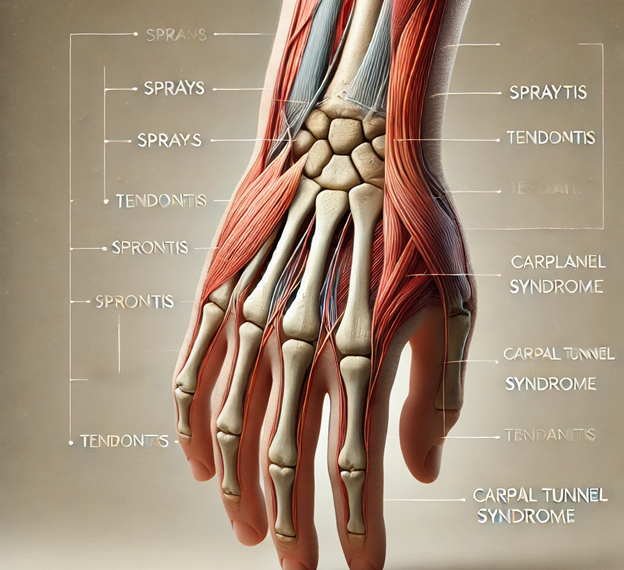

ساختار مچ دست و اهمیت آن

مچ دست از هشت استخوان کوچک تشکیل شده که با رباطها و تاندونها به یکدیگر متصل شدهاند. این استخوانها به دو استخوان اصلی ساعد (درشتنی و زند زیرین) متصل هستند و اجازه حرکتهای دقیق و انعطافپذیر را به دست میدهند.

مشکلات رایج مچ دست و علائم آنها

✅ التهاب تاندونها (تاندونیت): ناشی از فعالیتهای تکراری مانند تایپ کردن یا کار با ابزارهای دستی

✅ سندرم تونل کارپال، که باعث فشار روی عصب دست میشود

علائم کشیدگی تاندون مچ دست

کشیدگی تاندونها یکی از رایجترین مشکلات مچ دست است که معمولاً در اثر فشار زیاد یا حرکات ناگهانی رخ میدهد.

???? علائم کشیدگی تاندون مچ دست: